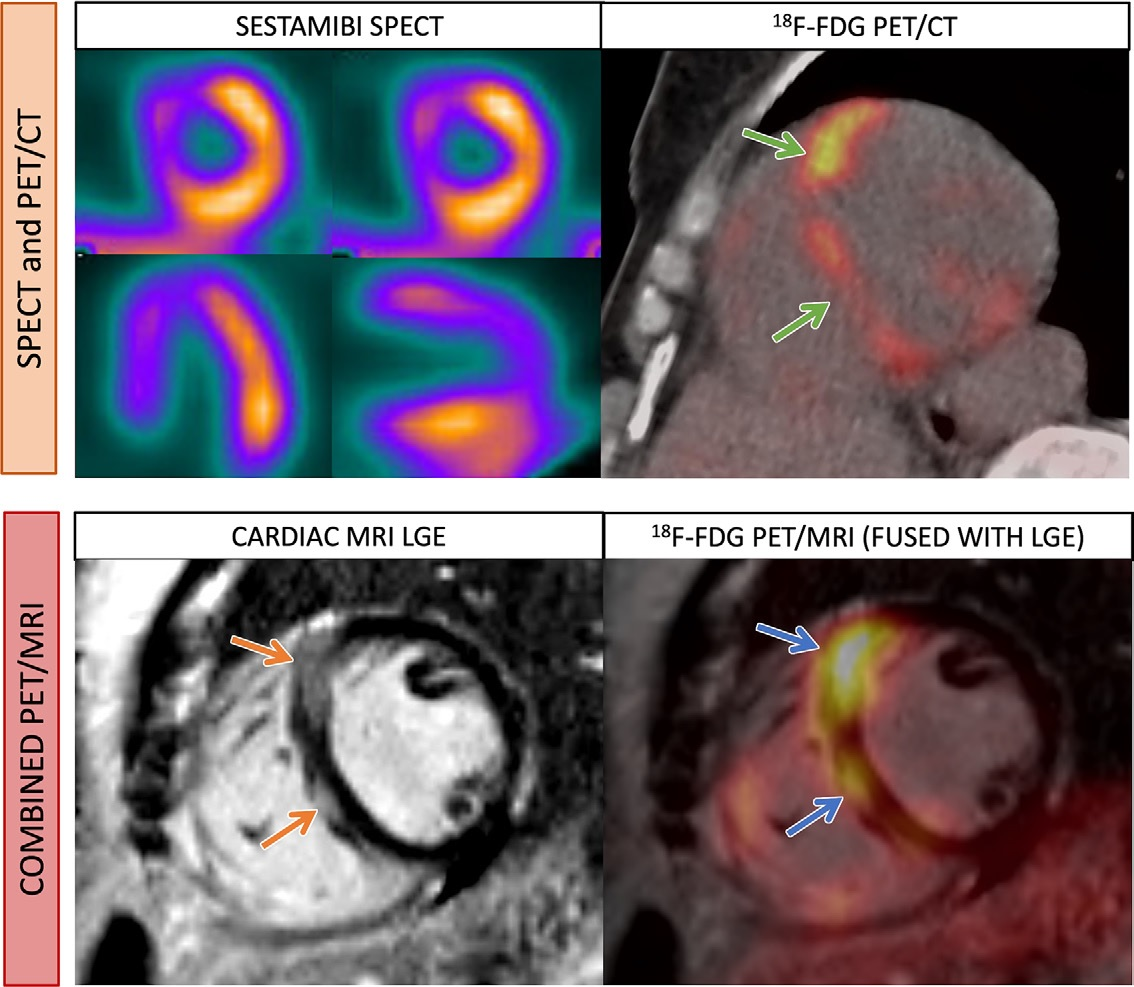

Cardiac sarcoidosis is characterized by the formation of granulomas in the tissue of the heart, and it can cause arrhythmias and heart failure. While there is no single diagnostic test for the disease (invasive biopsies are the most specific), PET imaging with FDG radiotracer is frequently used, as it identifies areas of cardiac inflammation. In addition, serial cardiac PET imaging is used to monitor how these patients respond to immunosuppression treatment.

A graphical abstract of the study. Image courtesy of JACC: Cardiovascular Imaging.